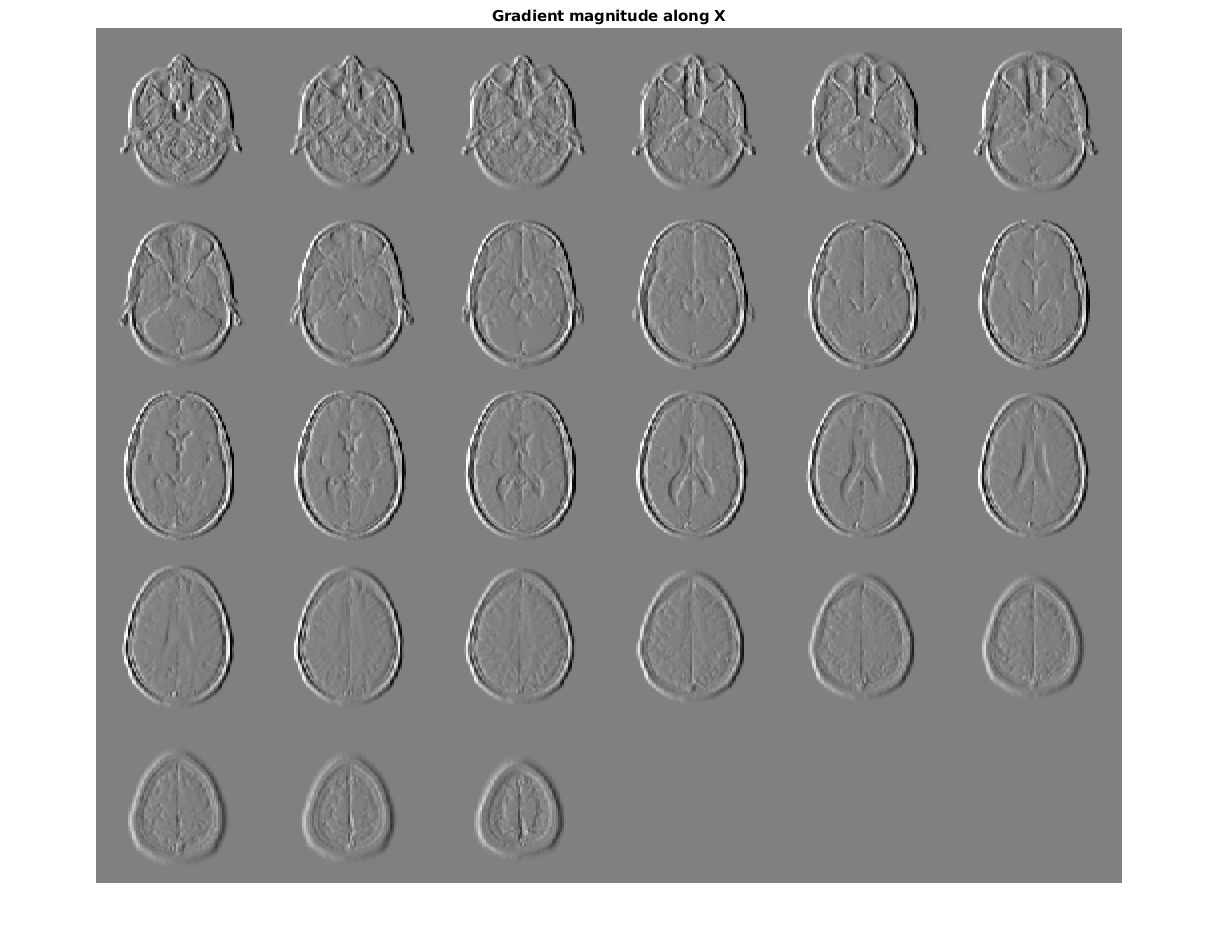

figure, montage(reshape(Gx,sz(1),sz(2),1,sz(3)),'DisplayRange',[])

title('Gradient magnitude along X')

Figure contains an axes. The axes with title Gradient magnitude along X contains an object of type image.